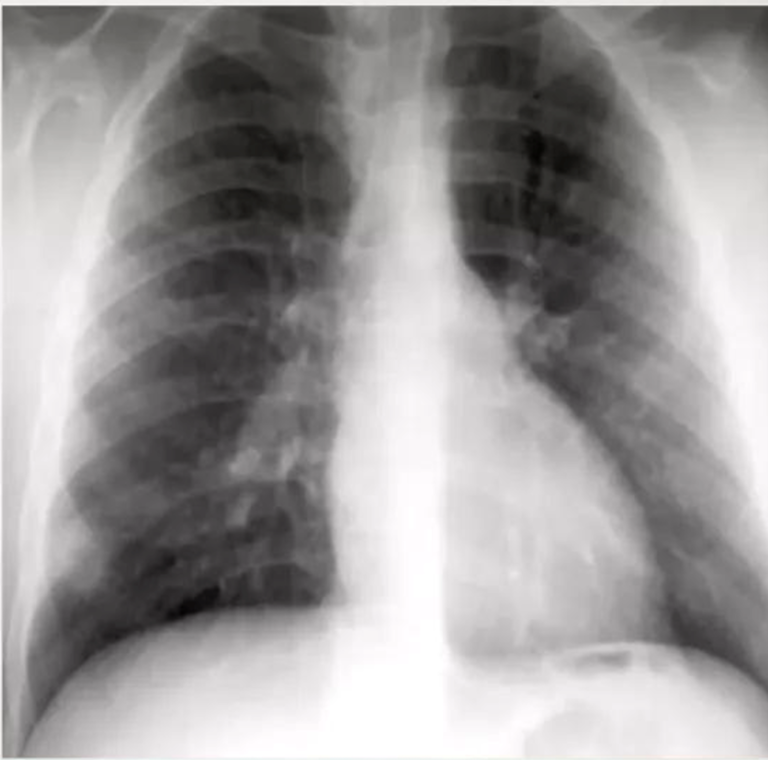

Pleural effusion is usually unilateral and due to subpleural infection.

Pleural effusions are more common in adults with primary tuberculosis (40%).

shows a right upper lobe airspace opacity adjacent to the trachea.